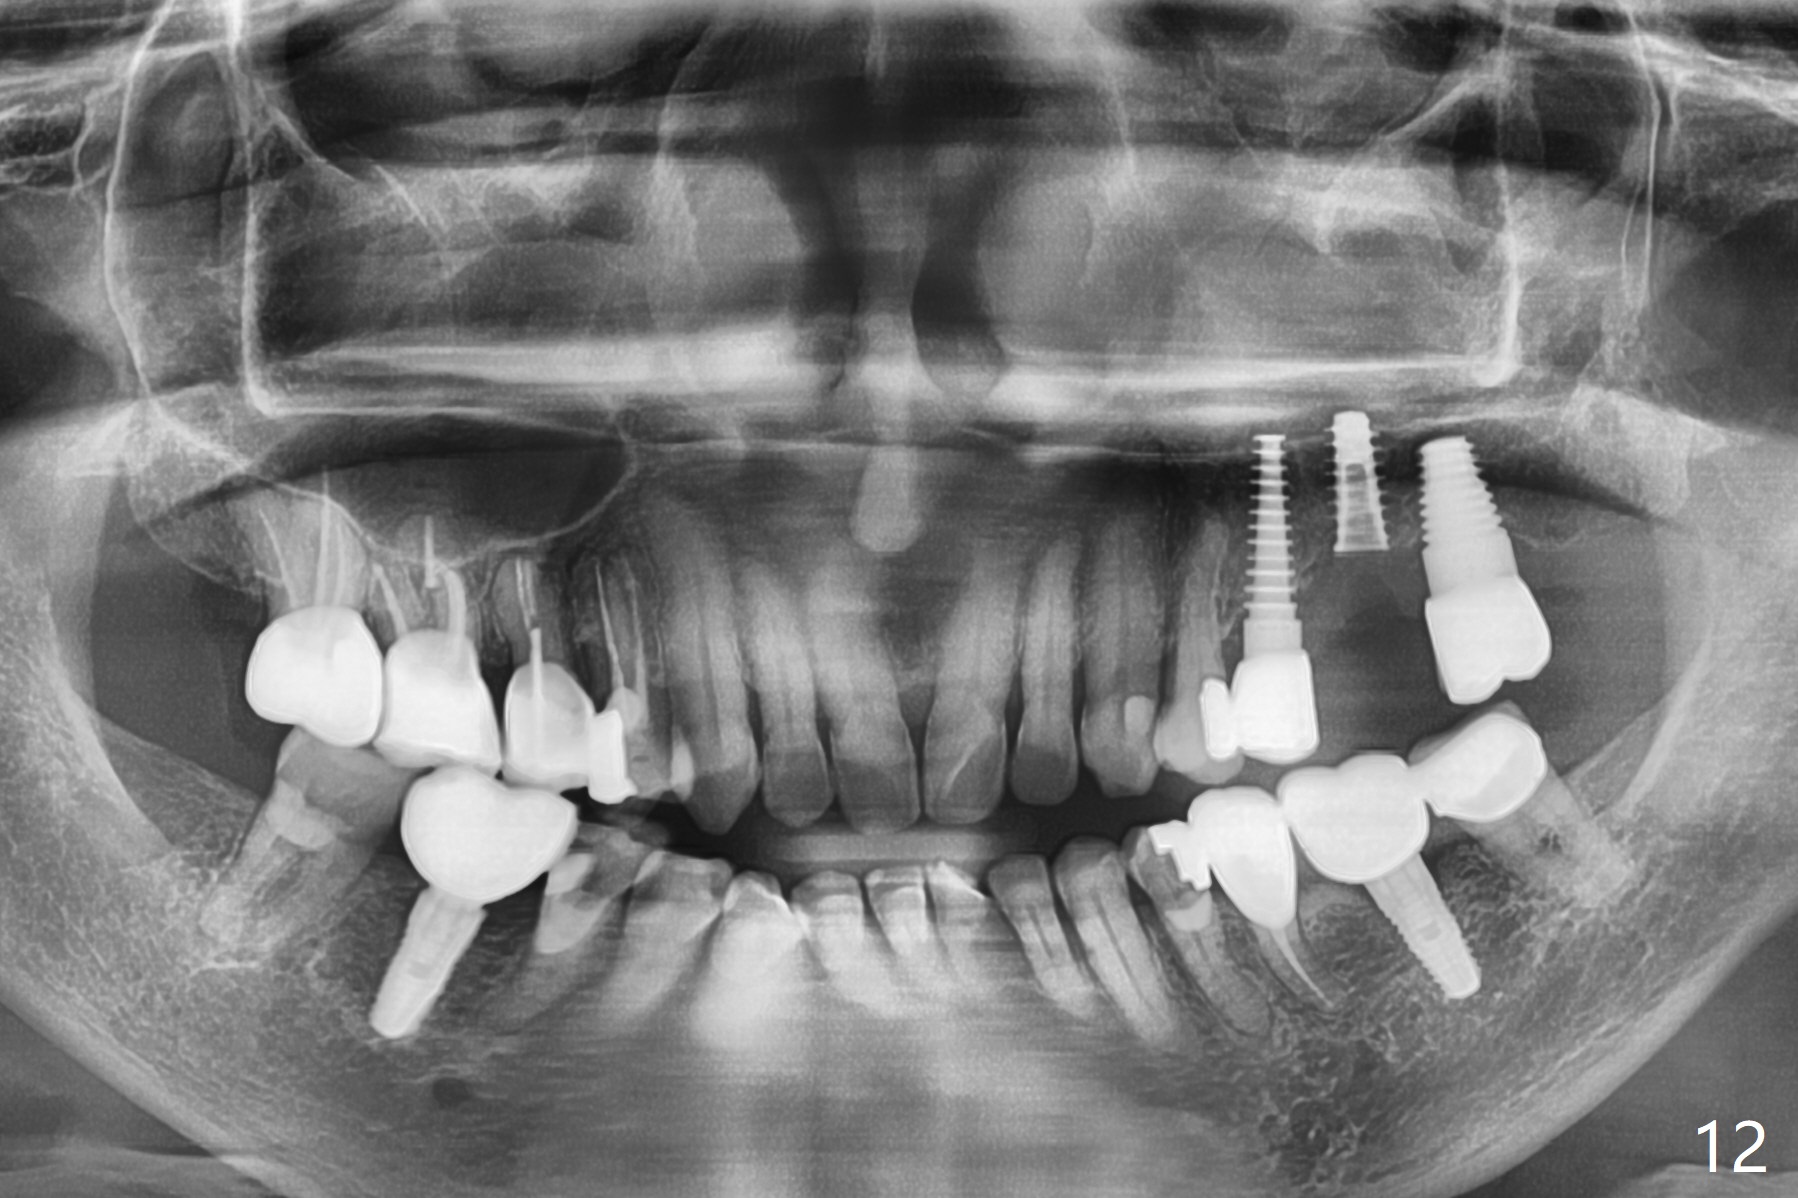

Initial osteotomy in the septum of the tooth #14 is 9 mm, approximately 2 mm from the sinus floor (Fig.1). Subsequent osteotomy depth is 11 mm, followed by insertion of a 4.5x11 mm dummy implant (Fig.2). After use of Magic Drill (MD) 4.8 mm for 9 mm, a 5x11 mm IBS implant is placed with sinus lift without additional bone graft (Fig.3 *). In contrast, autogenous bone (from MD) and Vanilla Graft are meticulously placed in the remaining socket (+) before and after placement of a 6.5x5.7(2) mm abutment. An immediate provisional is fabricated to close the sockets. There is buccal tenderness 1-3 months postop. There is distopalatal implant thread exposure. A healing abutment (5.5x2 mm) is placed. CT confirms thin buccal plate (Fig.4,5). It appears that the implant should have been as palatal as possible. The tenderness remains for the next 2 weeks. When the healing abutment is removed, the implant seems to have been placed shallow, ~ 1 mm subgingival (Fig.6). With local anesthesia, the implant is reversed to clean the coronal threads with Titanium brush and copious irrigation (Fig.7). The implant is then placed ~4 mm subgingival (Fig.8) and slightly subcrestal (Fig.9,10). It appears that the postop bone loss (Fig.9 *, as compared Fig.1,2) makes the implant look to be placed too shallow. When the implant is being placed deeper, the buccal plate feels intact. The early periimplantitis is apparently due to postop bone loss more than buccal placement, although certain degree of buccal bone resorption must occur. A 6x4 mm healing abutment is placed. Left facial swelling develops 2 days post implant elevation (Fig.11,12, as compared to preop (Fig.13)). The left maxillary sinus cloud (Fig.12) appears to be a false positive finding, since the same feature exists prior to implant elevation (Fig.13). Both sinuses look clear prior to implant elevation (Fig.14). Amoxicillin switches to Augmentin and Flagyl, since the patient is reluctant to have the implant removed. Finally the sinus infection is under control. The patient feels left facial swelling 9 months postop (5 months post elevation) and reports left nasal discharge ~ 1 month earlier. There is mild buccal plate tenderness. The implant seems to be buccally placed (Fig.15,16), although there is no significant change radiographically (Fig.17). The implant is removed with bone graft (Fig.18 *). To avoid complication and failure, an immediate implant at the upper 1st molar should be short and placed deep.